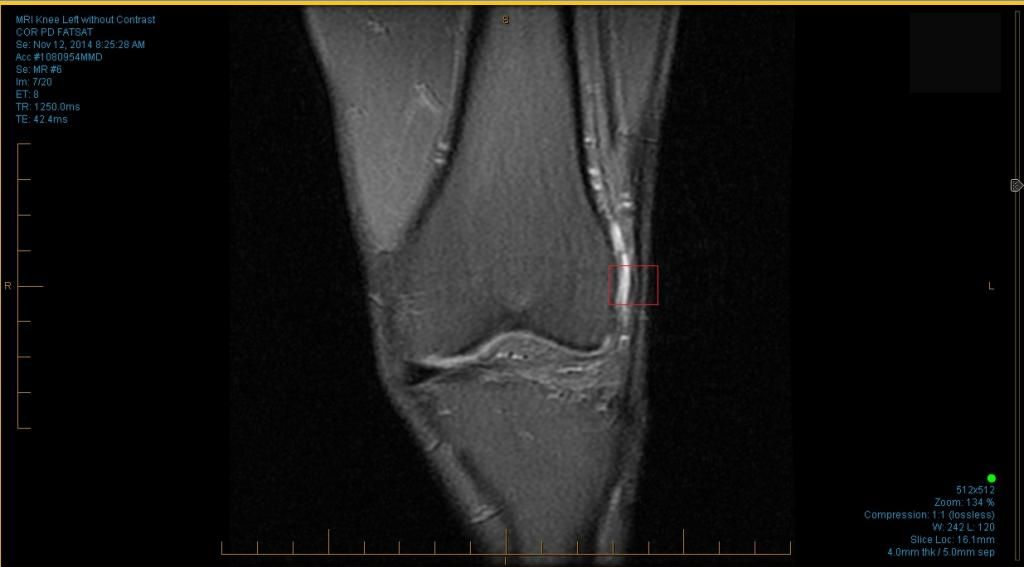

All I know is light colors could signify fluid…the light color is also whee i experience pain.

recently by just feeling around, it seems there is a sharp corner on the outside of my left knee (IT band injured)…which feels more blunt on my right knee.

i tried looking for the corner in my images…and this is the best thing i could come up with (first image below with the red box).

I can read an MRI. It looks like your IT band is unhappy. You already knew that. Unfortunately the MRI can’t tell you how to fix it.